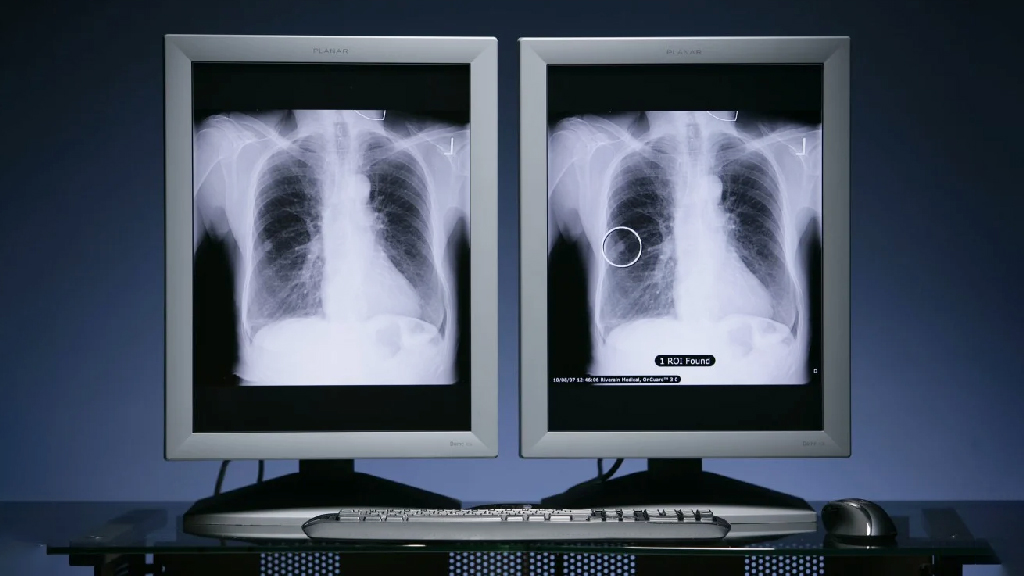

চীনা ও মার্কিন বিজ্ঞানীদের নেতৃত্বে একধরনের জটিল ফুসফুস ক্যানসারের চিকিৎসায় নতুন একটি ওষুধের আন্তর্জাতিক ক্লিনিক্যাল ট্রায়াল চলছে। এই ট্রায়ালে ইতিমধ্যে প্রমাণ পাওয়া গেছে, মুখে খাওয়ার ওই ওষুধ আগের চিকিৎসার তুলনায় বেশি নিরাপদ ও কার্যকর।বিস্তারিত

চীনা ও মার্কিন বিজ্ঞানীদের নেতৃত্বে একধরনের জটিল ফুসফুস ক্যানসারের চিকিৎসায় নতুন একটি ওষুধের আন্তর্জাতিক ক্লিনিক্যাল ট্রায়াল চলছে। এই ট্রায়ালে ইতিমধ্যে প্রমাণ পাওয়া গেছে, মুখে খাওয়ার ওই ওষুধ আগের চিকিৎসার তুলনায় বেশি নিরাপদ ও কার্যকর।বিস্তারিত

চীনা ও মার্কিন বিজ্ঞানীদের নেতৃত্বে একধরনের জটিল ফুসফুস ক্যানসারের চিকিৎসায় নতুন একটি ওষুধের আন্তর্জাতিক ক্লিনিক্যাল ট্রায়াল চলছে। এই ট্রায়ালে ইতিমধ্যে প্রমাণ পাওয়া গেছে, মুখে খাওয়ার ওই ওষুধ আগের চিকিৎসার তুলনায় বেশি নিরাপদ ও কার্যকর।বিস্তারিত

চীনা ও মার্কিন বিজ্ঞানীদের নেতৃত্বে একধরনের জটিল ফুসফুস ক্যানসারের চিকিৎসায় নতুন একটি ওষুধের আন্তর্জাতিক ক্লিনিক্যাল ট্রায়াল চলছে। এই ট্রায়ালে ইতিমধ্যে প্রমাণ পাওয়া গেছে, মুখে খাওয়ার ওই ওষুধ আগের চিকিৎসার তুলনায় বেশি নিরাপদ ও কার্যকর।বিস্তারিত